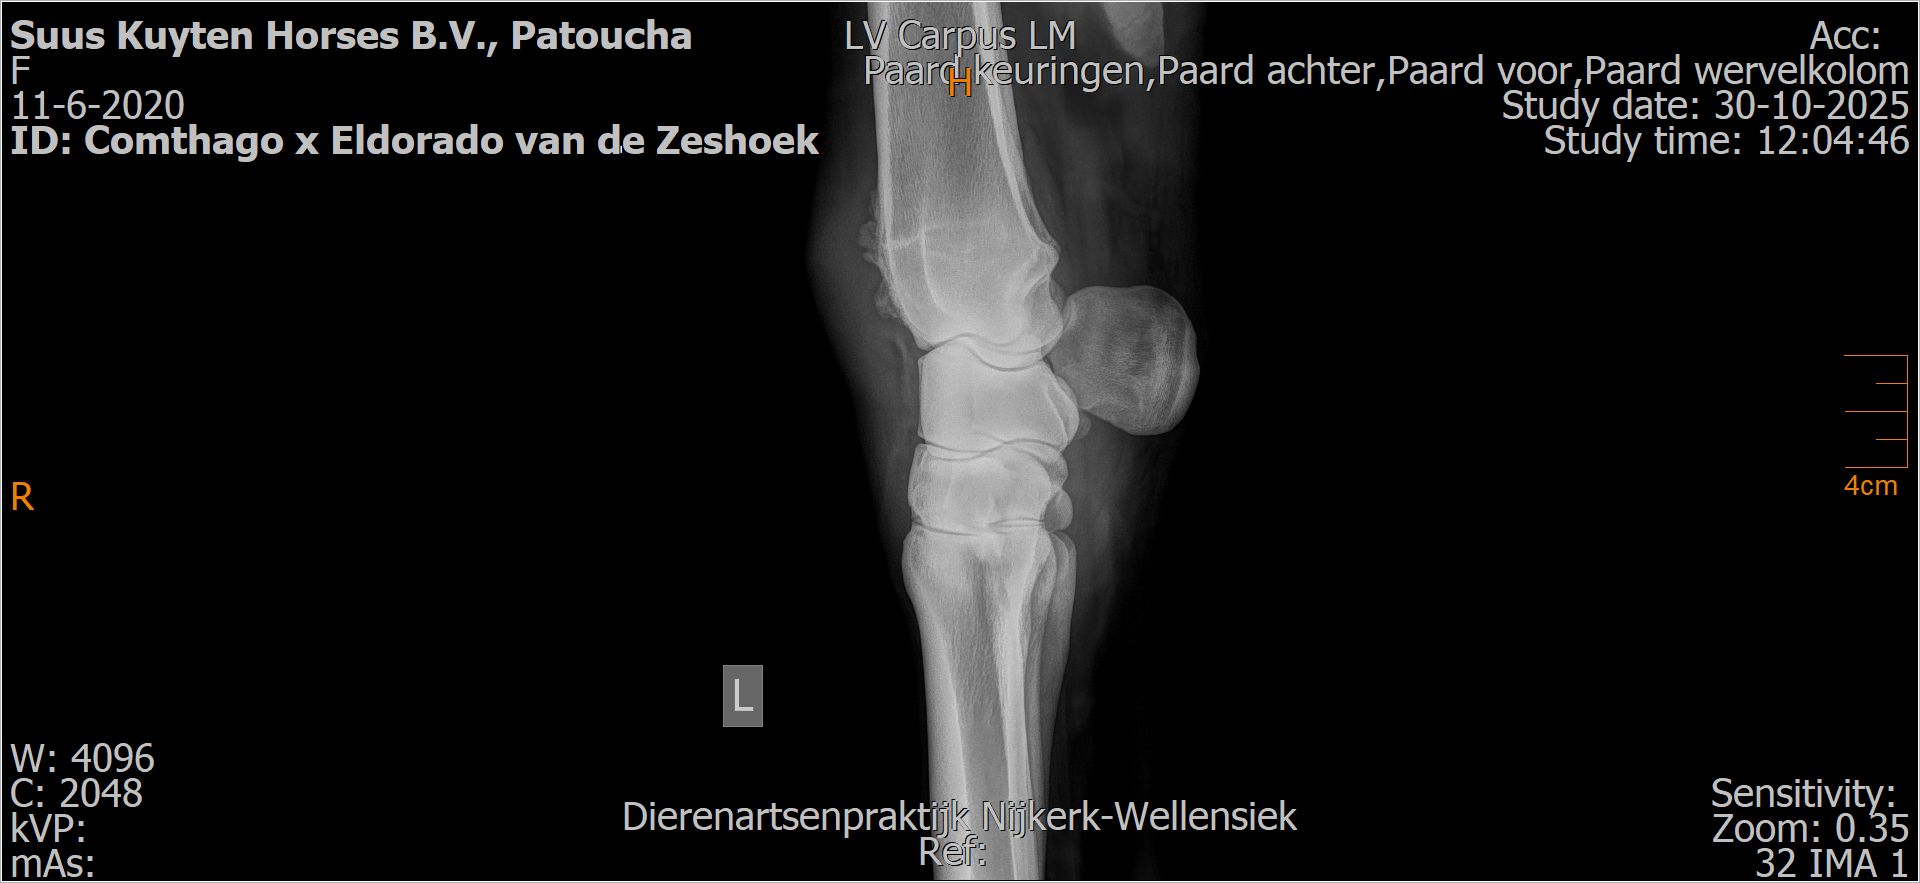

Patoucha

Leeftijd:

7

Röntgenfoto’s